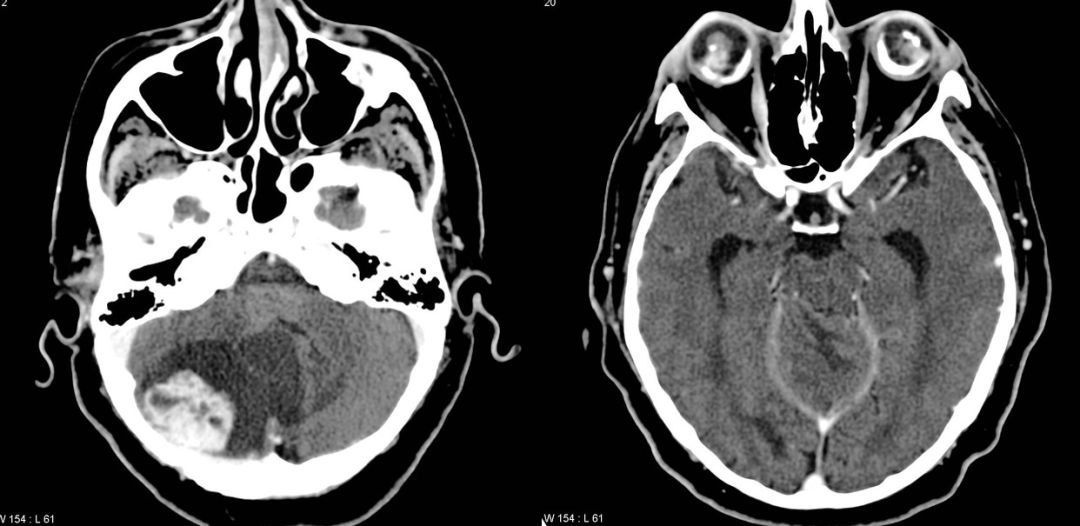

先天性CMV感染

先天性巨细胞病毒感染